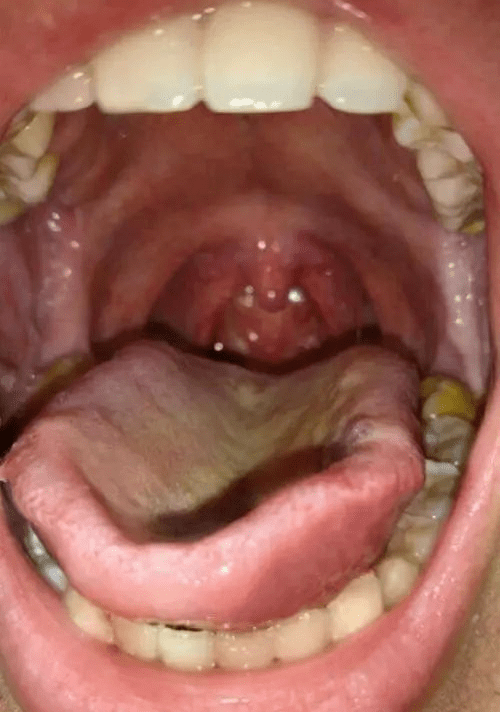

一样吗,我感觉我的和别的都不一样啊 大家帮我看看我的喉咙结构正常吗

请问我的喉咙里有黄色的脓包一块块一粒粒的是什么啊是什么原因啊?

发炎吗喉咙?那喉壁小红肉是什么

喉咙长得东西好像滤泡咽喉炎,干痒,咳嗽.

我喉咙里那个水泡是什么情况?淋巴泡增生吗?如何治疗?如何保养?

喉咙里为啥是这样?